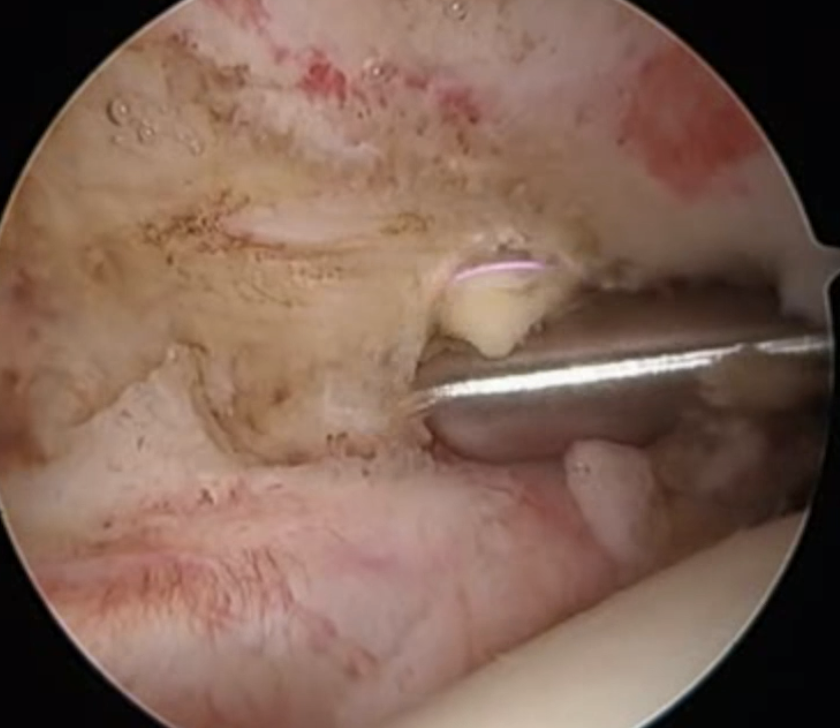

Full thickness tear of subscapularis off insertion revealed with grasper